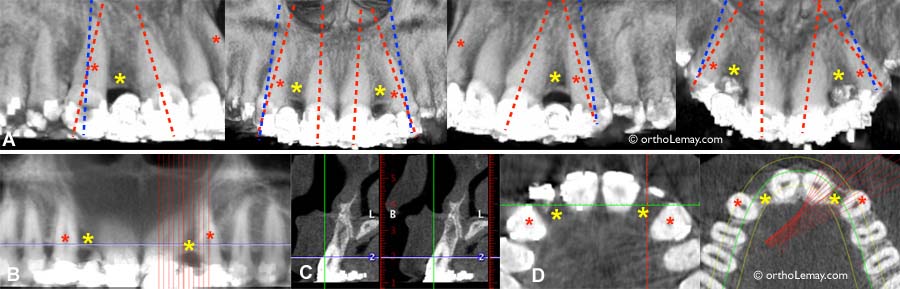

Utilisation de radiographies volumiques tridimensionnelles pour évaluer la position des racines des canines et des incisives latérales supérieures en prévision de la pose d’implants dentaires pour remplacer les incisives latérales manquantes (* jaune). (A) Les pointillés rouges indiquent l’axe (inclinaison) des dents avant le traitement et les pointillés bleus représentent la position idéale que devraient avoir les incisives latérales pour permettre la pose d’implants sans interférer avec les racines des dents. (B) Des coupes à la fraction de millimètre près permettent d’évaluer l’os et les racines. (C) Vue en coupe de côté (sagittale). (D) Vue en coupe axiale (vue occlusale) à travers les couronnes et les racines montrant l’espace et l’os entre les dents.